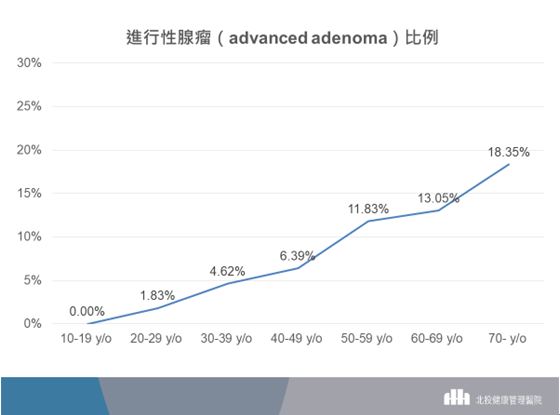

依照北投健康管理醫院內視鏡中心資料更進一步看看與未來大腸直腸癌有關的腺瘤息肉的比例,整體有腺瘤息肉的比例為36.2%(圖二),30-39歲的族群有腺瘤息肉的比例為18.3%,而40-49歲的族群有腺瘤息肉的比例也有32.6%。當然,與大腸直腸癌更相關的進展型腺瘤息肉,30-39歲的族群的比例為4.62%,而40-49歲的族群的比例也有6.39%(圖三)。

▲(圖三)以歷年統計資料來看,30-39歲的族群有進行性腺瘤的比例為4.62%,而40-49歲的族群有進行性腺瘤的比例也有6.39%